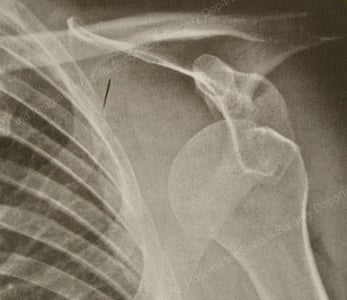

X-ray image of glenohumeral (GH) dislocation